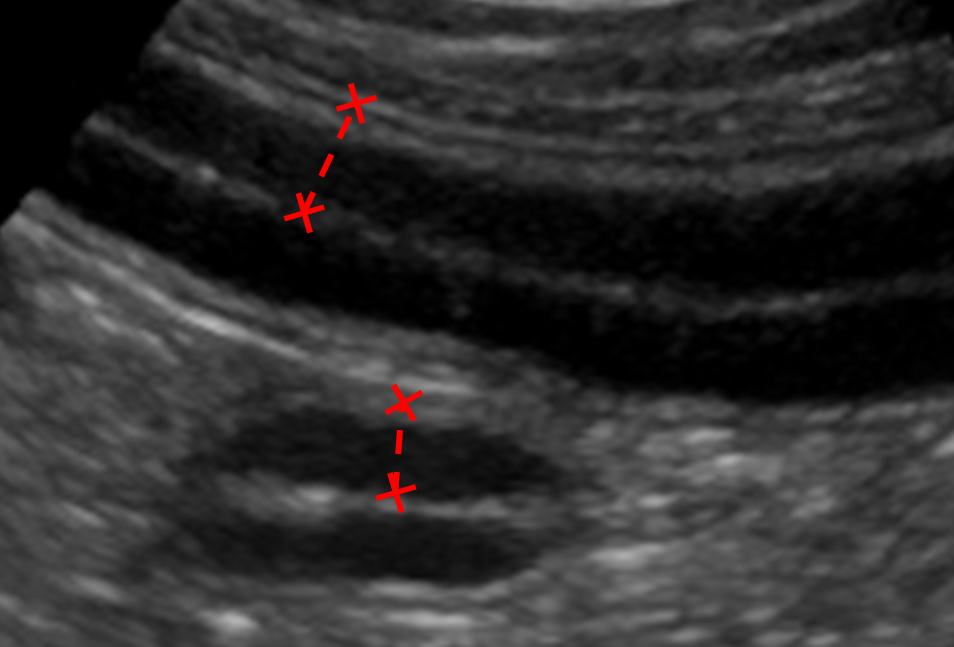

Gastrointestinal wall thickness is measured from the inner edge of the mucosal layer outwards to the outer edge of the muscularis layer (Figure 3).

Figure 3. An ultrasound image showing 2 sections of small intestine. Two callipers (crosses with linked dotted line) have been placed to measure intestinal wall thickness, from the inner edge of the mucosa outwards to the outer edge of the muscularis layer.